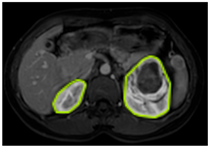

3.2.1. ROI Dataset

The images used in the study include different anatomical areas, such as the liver, spleen, and intestine. However, in order to process the data more quickly and provide more accurate results from the analysis, only the kidney areas (Regions of Interest, ROI) were extracted and evaluated. The Roboflow platform was used for spatial matching and segmentation of the kidneys. Polygonal ROI regions were defined by applying the semantic segmentation method, and then the transformations performed were verified by the radiologist, increasing the reliability of the system. In our study, MRI phase images were acquired at a resolution of 512 × 512 and the renal region of interest (ROI) was segmented and resized to 224 × 224 for input into the DenseNet architecture. In a similar study, Alhussaini et al. utilized 512 × 512 CT images and processed tumor-containing ROIs for their analysis; however, segmented region details were not provided [23]. Another study aimed to differentiate ccRCC from oncocytoma by extracting ROIs from T2-weighted images (T2-WI), pre-contrast T1-weighted images (T1-WI), and post-contrast arterial and venous phases. Tumor regions segmented at 100 × 100 mm were subsequently resized for input into the AlexNet model [24]. Unlike these studies, our approach involves segmenting the entire kidney, rather than solely the tumor region, to enable the deep learning model to leverage structural information for the organ as a whole.

Table 2 shows sample images containing ROI areas for different phases.

Table 2.

ROI areas in different phases.